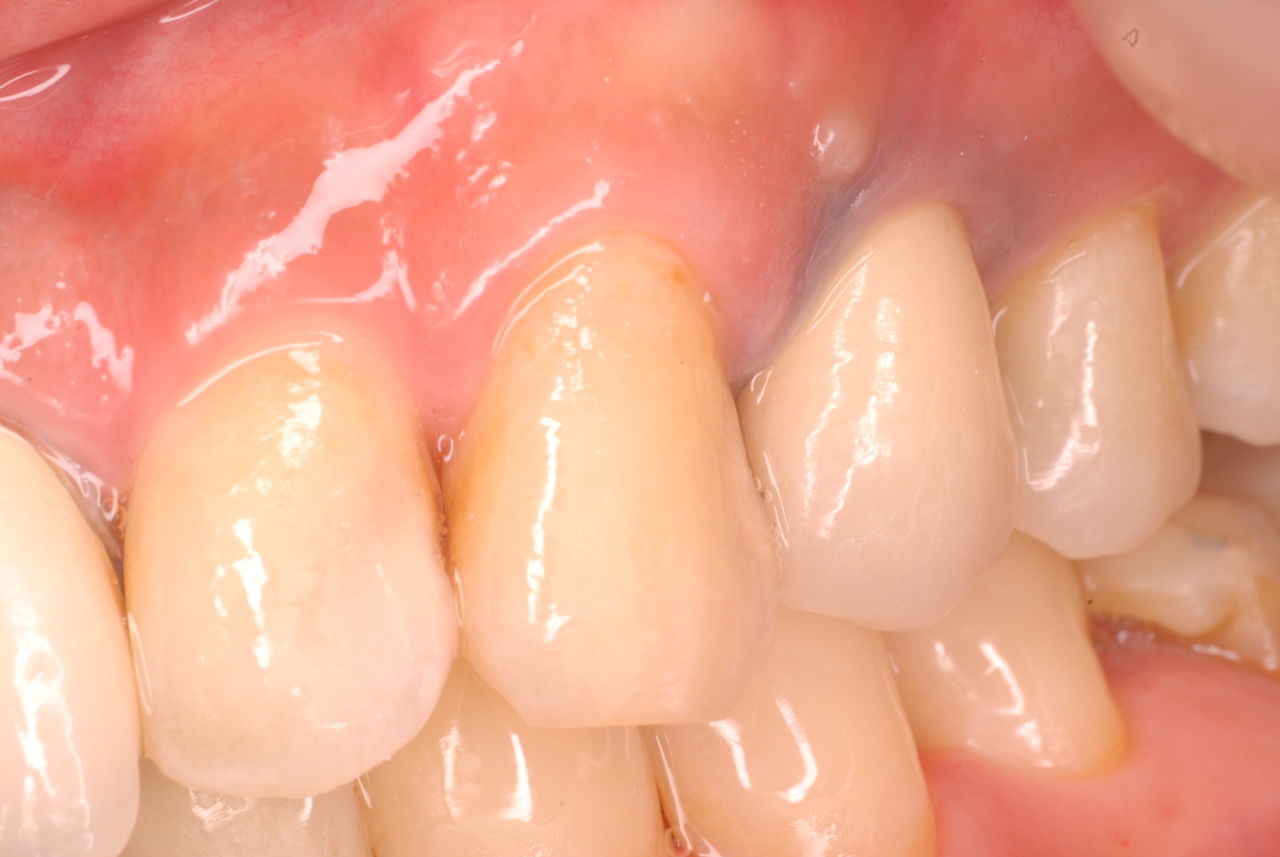

ご自分でやられても歯茎から血が出ないと話をされていましたが、私がブラシを当てると悲惨な状態であることがわかりました。

何故歯が悪くなるのか、歯周病で抜けるのか分からなければ何を入れても歯は悪くなり抜けていくのです。

病気を治しましょう。それから差し歯や入れ歯を入れましょう!物を入れれば入れるほど、磨き方や掃除の仕方が上手にならなければ、すぐ抜けてくるのです。